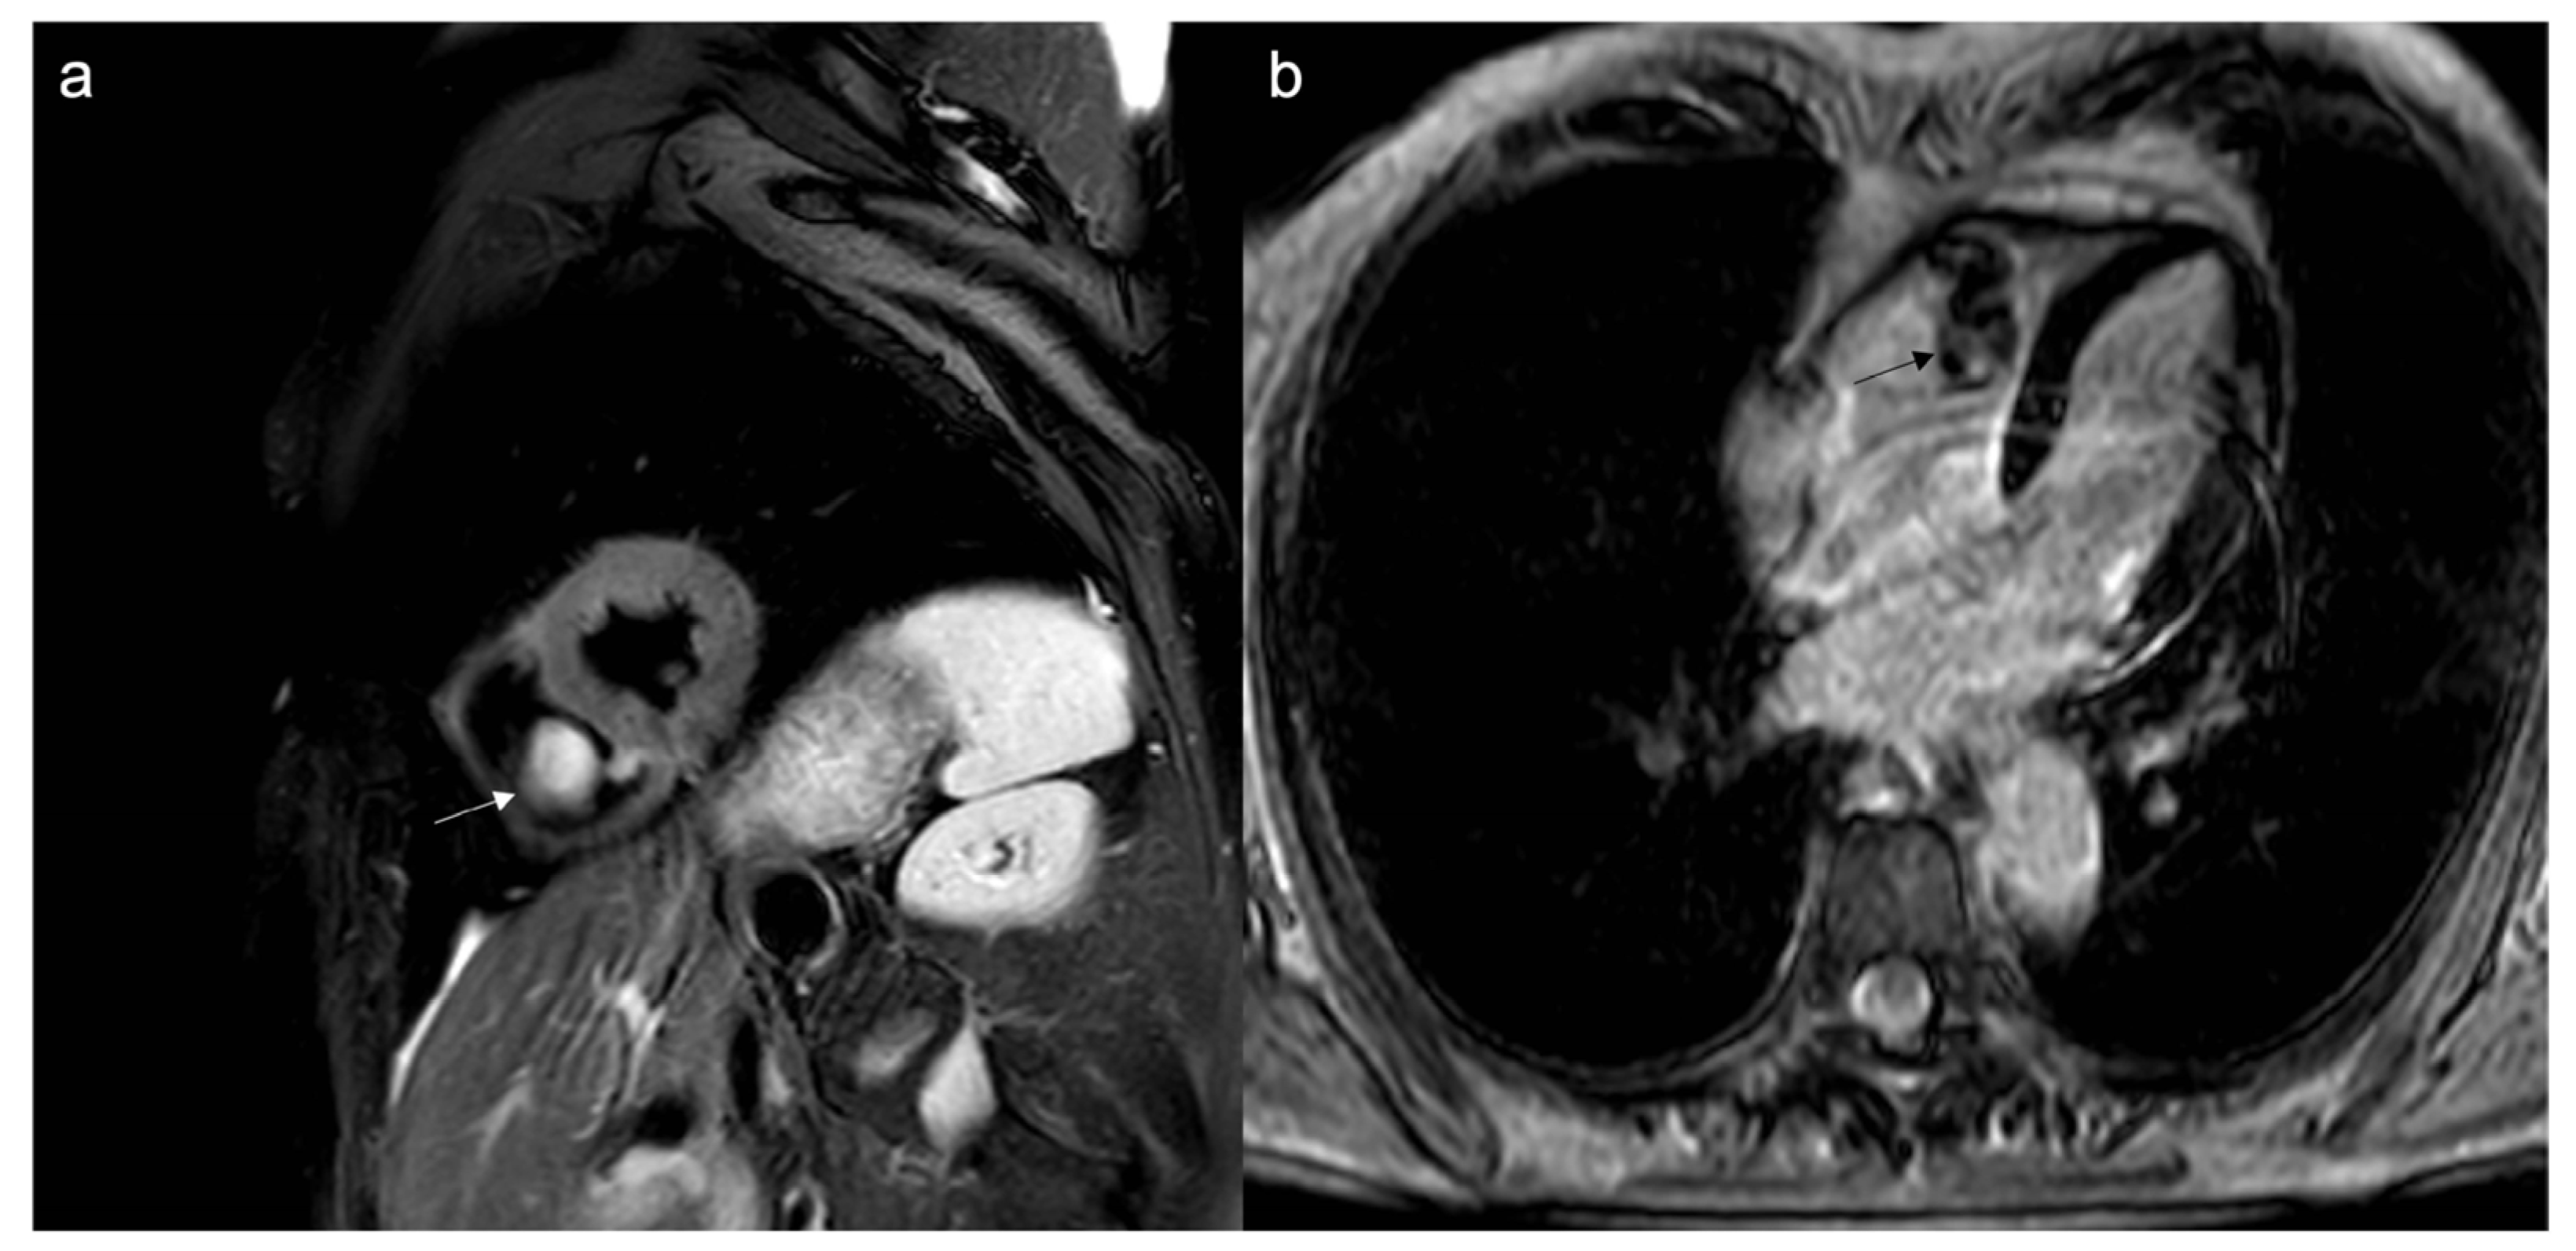

- Malignant masses often show heterogeneous enhancement; typically, angiosarcoma shows early avid enhancement as it is richly vascularized.

- Trombi due to their avascular nature appear non-enhanced.

- Organized thrombi may show peripheral enhancement on LGE images, owing to their fibrous content.